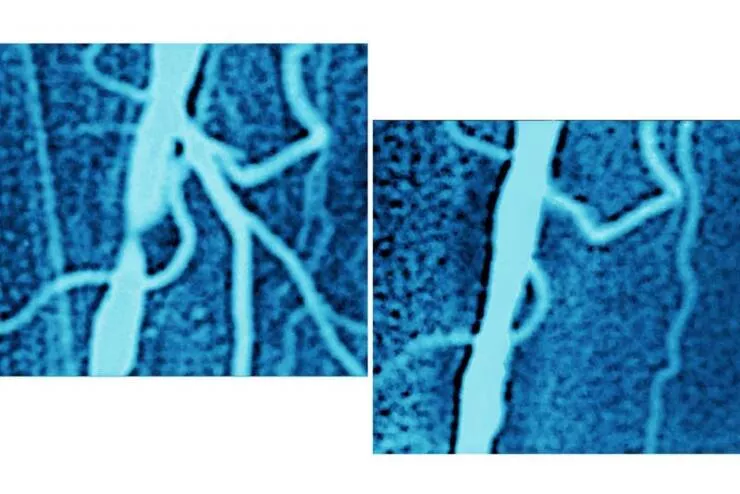

#25 And a patient's iliac artery before and after an angioplasty procedure: